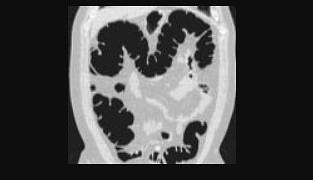

Early detection of polyps has proven to lead to a decrease in incidence of colon cancer. In the past few years, virtual colonoscopy has been developed as a patient-friendly screening technique. The procedure comprises the following steps. First, the patient's colon is cleansed and transanally inflated with air. Subsequently, a 3D image volume is acquired of the abdomen by CT or MRI. Finally, the bowel surface is extracted and visualized, after which the physician virtually navigates through the colon and examines the surface for abnormalities. This paper describes the progress in research for virtual colonoscopy.